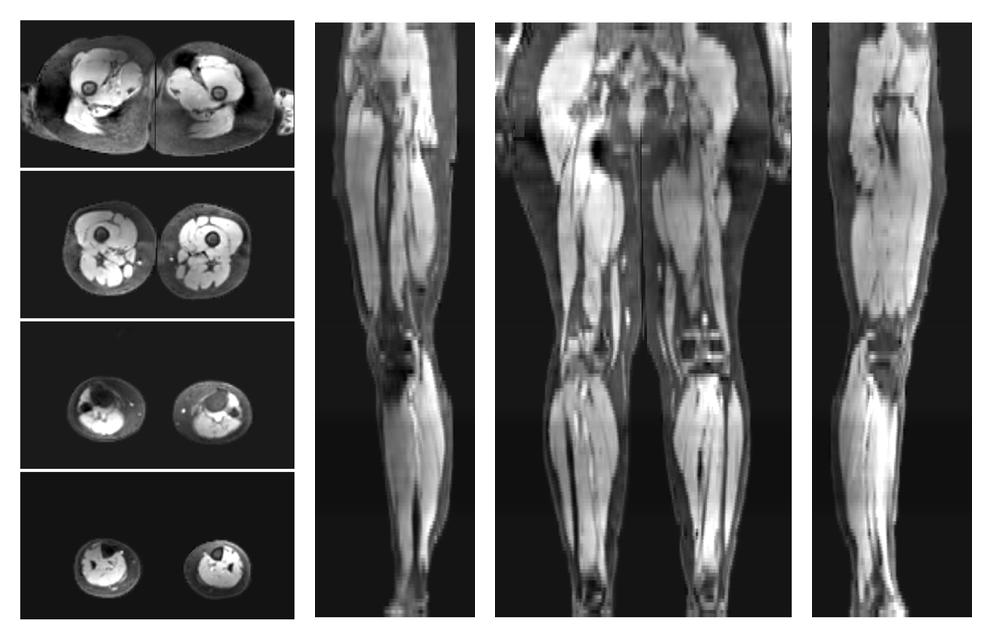

• Water only signal

The water part of the acquired multi-echo spin echo data.

• Water only T2 relaxation time

The water only T2 relaxation time of the lower extremity obtained from multi echo spin echo t2 mapping with EPG based reconstruction.